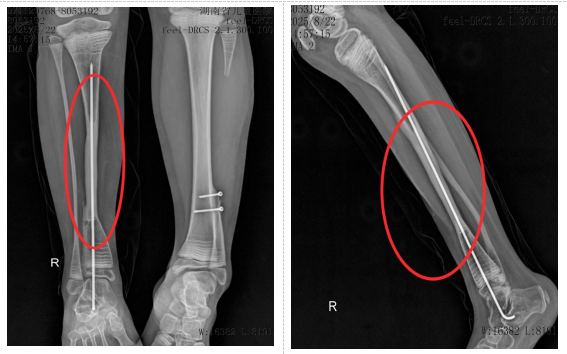

小小出生3个月时即发现右小腿下段弯曲,2岁时因胫骨骨折辗转于数家医院,经多次手术失败后经人推荐来湖南省儿童医院治疗。先天性胫骨假关节导致小小右侧胫骨出现大段骨缺损,传统治疗方法效果有限,且存在肢体短缩、畸形甚至截肢的风险。面对这一棘手难题,湖南省儿童医院骨科团队经过多次病例讨论和精密规划,决定实施一项新的手术方案:“右侧胫骨内固定取出,右侧胫骨假关节病变切除,取左侧带血管蒂的腓骨移植,克氏针髓内固定,伊氏架外固定,左侧胫腓骨远端融合,石膏托外固定术”。即从小小健康的左侧小腿取一段带血管蒂的腓骨,移植到右侧胫骨缺损处,通过吻合血管重建移植后的腓骨血运,重建胫骨的完整性与支撑功能。

术前

术后